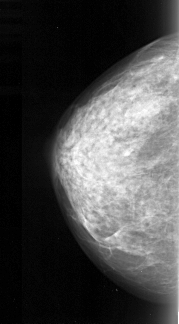

A_1057_1.RIGHT_MLO

RIGHT_MLO LINES 5266 PIXELS_PER_LINE 2596 BITS_PER_PIXEL 16 RESOLUTION 42 OVERLAY